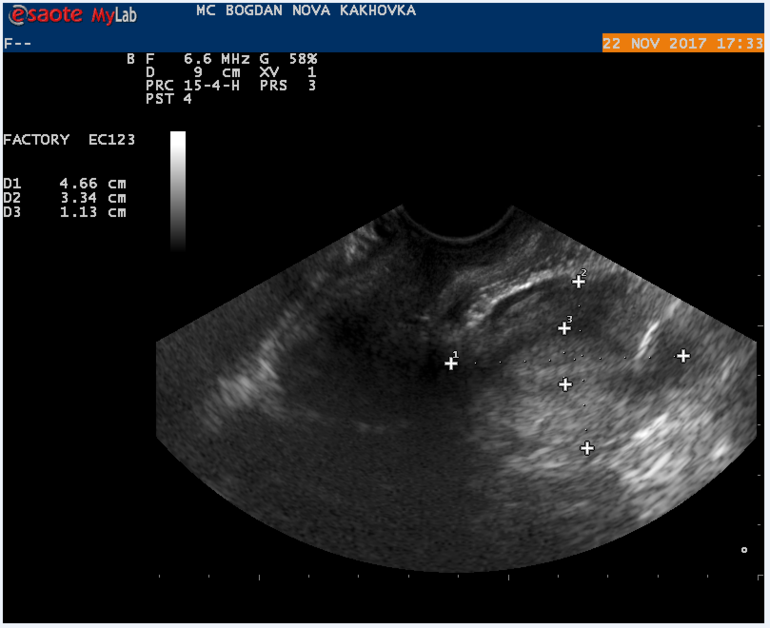

Мой результат УЗИ на 16 ДЦ Кто что может сказать? Тест на О положительный на 13 и 14 ДЦ.

Могли желтое тело не увидеть, а мог и сдуться фоликул, и не было овуляции. А то что эндометрий хороший - еще не показатель, у меня при здутии фолликула и при лютеинизации фолликула он тоже был отличный и соответствовал второй фазе.

Может не увидели жт? Или не успело сформироваться.. Лично не сталкивалась, но читала, что бывает его не видят. Ведь эндик второй фазы у вас.

Какой день имел в виду Г? 1 дпо? По идее узи должно хорошо отображать картину в любой день.. Но просто видимо бывает, что узист что-то не разглядит, может аппарат не очень. У вас О вероятно была на 15 дц. А до этого не делали узи в этом цикле? Для точности О можно и прогик сдать. Но нам важнее конечно хгч))

в протоколе узи не слова о наличии доминантного фолликула, поэтому вряд ли была или будет овуляция в ближайшие дни

судя по узи овуляции не было,доминантного фолликула нет. хотя желтое тело может позже сформироваться